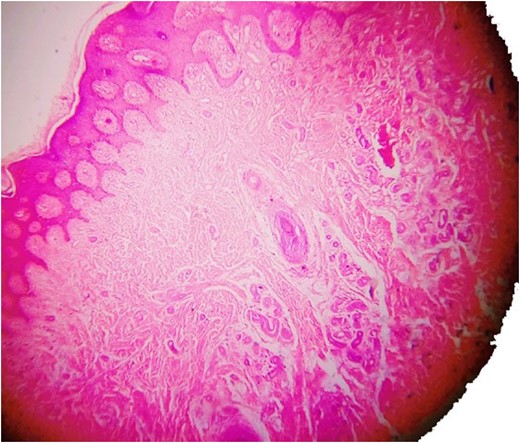

The superficial layer of the lesion showing angiokeratoma (haematoxylin and eosin).

Histopathology examination revealed grayish white to grayish brown lesions with hyperkeratitis of the epidermis and focally hyperplastic stratified squamous epithelium. Papillary dermis with numerous dilated, thin walled congested capillaries and the deep dermis with increased number of eccrine glands and numerous capillary channels intermingled with eccrine structure. The stroma was composed of fibrofatty tissue along with few pilar structures with the focal distribution of granulation tissue. Such a histological picture was found to be consistent with a diagnosis of EAKH.